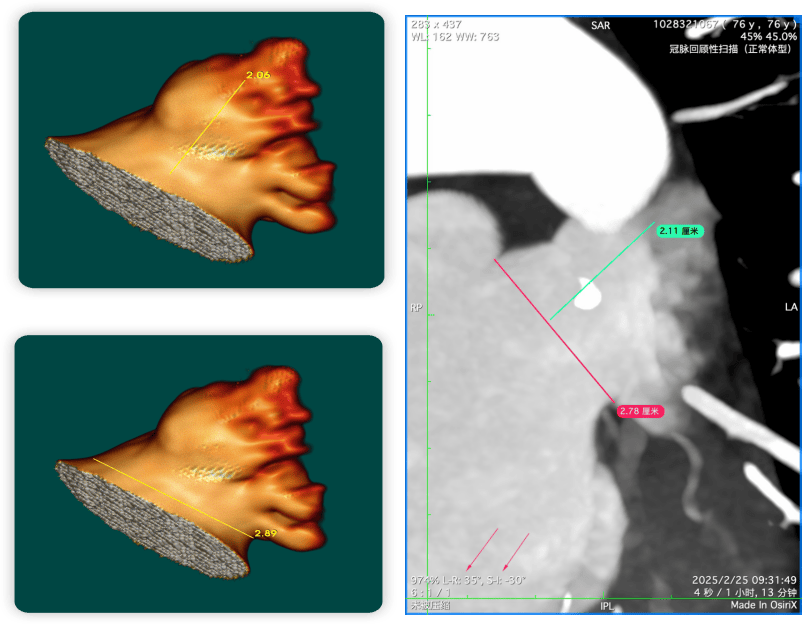

左心耳cta测量